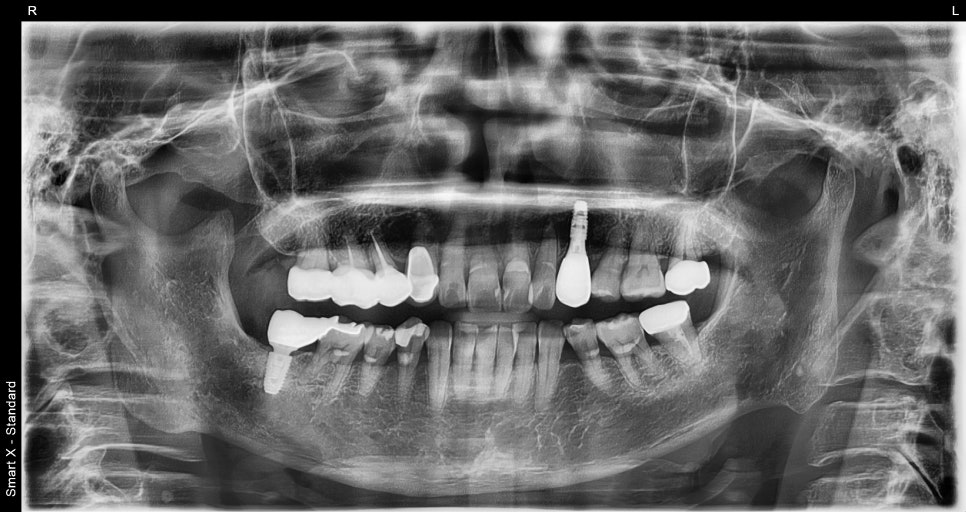

📸 최종 파노라마

앞니 임플란트 완성 후 파노라마 사진

픽스처(임플란트 뿌리)가 잇몸뼈에 잘 자리잡은 걸 확인하고

자연치와 잘 어울리는 앞니 보철물을 제작해드렸어요.